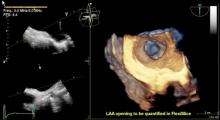

Enhanced features on the Philips EPIQ CVx ultrasound system provide a next level photorealistic 3D rendering, making it easy for users to interpret what they are seeing. The TrueVue feature enhances the sense of depth and space, producing images that appear natural and realistic to the human eye.

Watch the video to check out how TrueVue can help improve views of LAA and MV morphology.